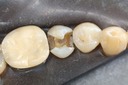

Kyle Chock #14 amalgam removal